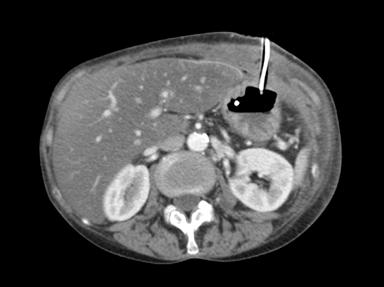

Despite an uneventful PEG-J insertion, the patient returned to the ward complaining of intense pain at the PEG site. Perforation was suspected, and the patient commenced on prophylactic antibiotics. However, a CT scan confirmed correct placement of the PEG-J, although the tract appeared slightly wider than anticipated (Figure 2).

|

Figure 2. CT scan following PEG-J insertion. |